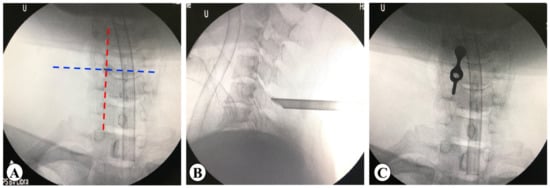

2.3.2. PE